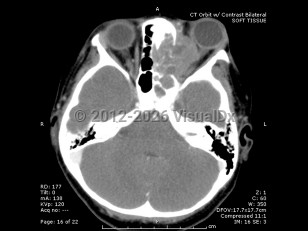

Orbital rhabdomyosarcoma - External and Internal Eye

Rhabdomyosarcoma is a rare childhood cancer that affects approximately 350 children per year in the United States, with 10% of cases involving the orbit. Rhabdomyosarcoma is the most common primary orbital tumor in childhood. Patients usually present between 5 and 10 years of age, with boys having a higher incidence than girls.

Proptosis is the most common presenting sign and may develop over the course of just a few days or a month. Often there is a history of recent trauma upon presentation of the tumor, which may lead to confusion with the diagnosis. Orbital rhabdomyosarcoma sometimes presents with strabismus or as a localized eyelid or conjunctival mass.